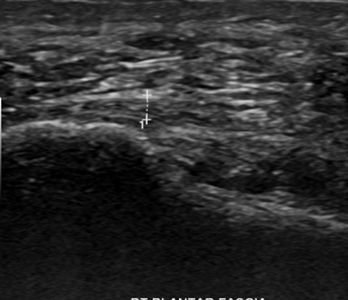

족저근막염

여성 족저근막염

60세

여성 지간신경종

44세

남성 족저근막염